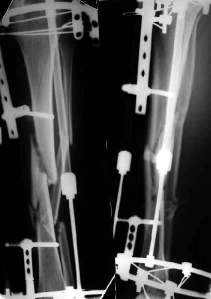

Re: Неправильно сросшийся перелом голени

Александр Николаевич, к сожалению больной не является на контрольные осмотры. Я последний раз видел больного, когда прошло 7 месяцев после операции БОС. У него все хорошо. Каких либо жалоб и ограничений в нагрузке нет. Высылаю снимки до операции и последние снимки.